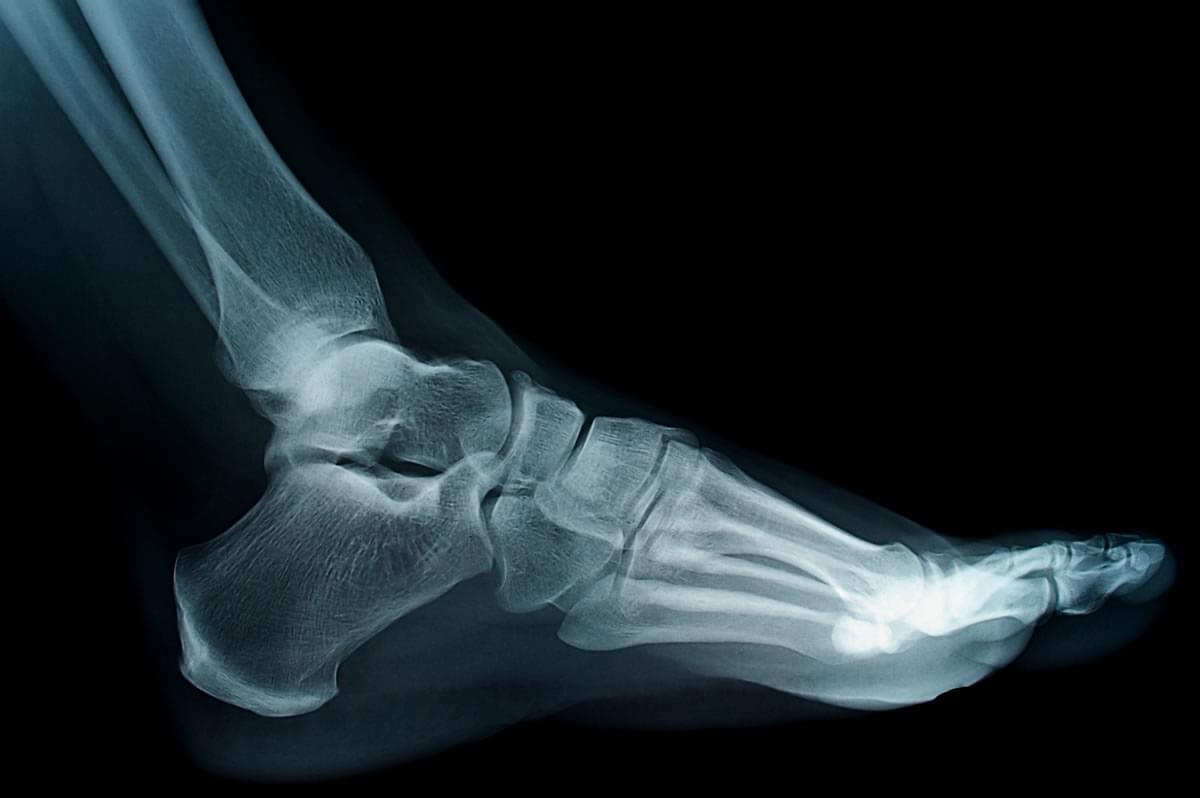

By having X-rays in my office, I can quickly assess your problem and follow your progress. This eliminates unnecessary visits to the office and prevents delaying treatment for your ailment.